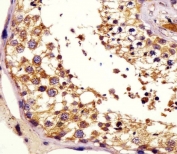

IHC testing of FFPE human testis tissue with KiSS-1 antibody. HIER: steam section in pH6 citrate buffer for 20 min and allow to cool prior to staining.